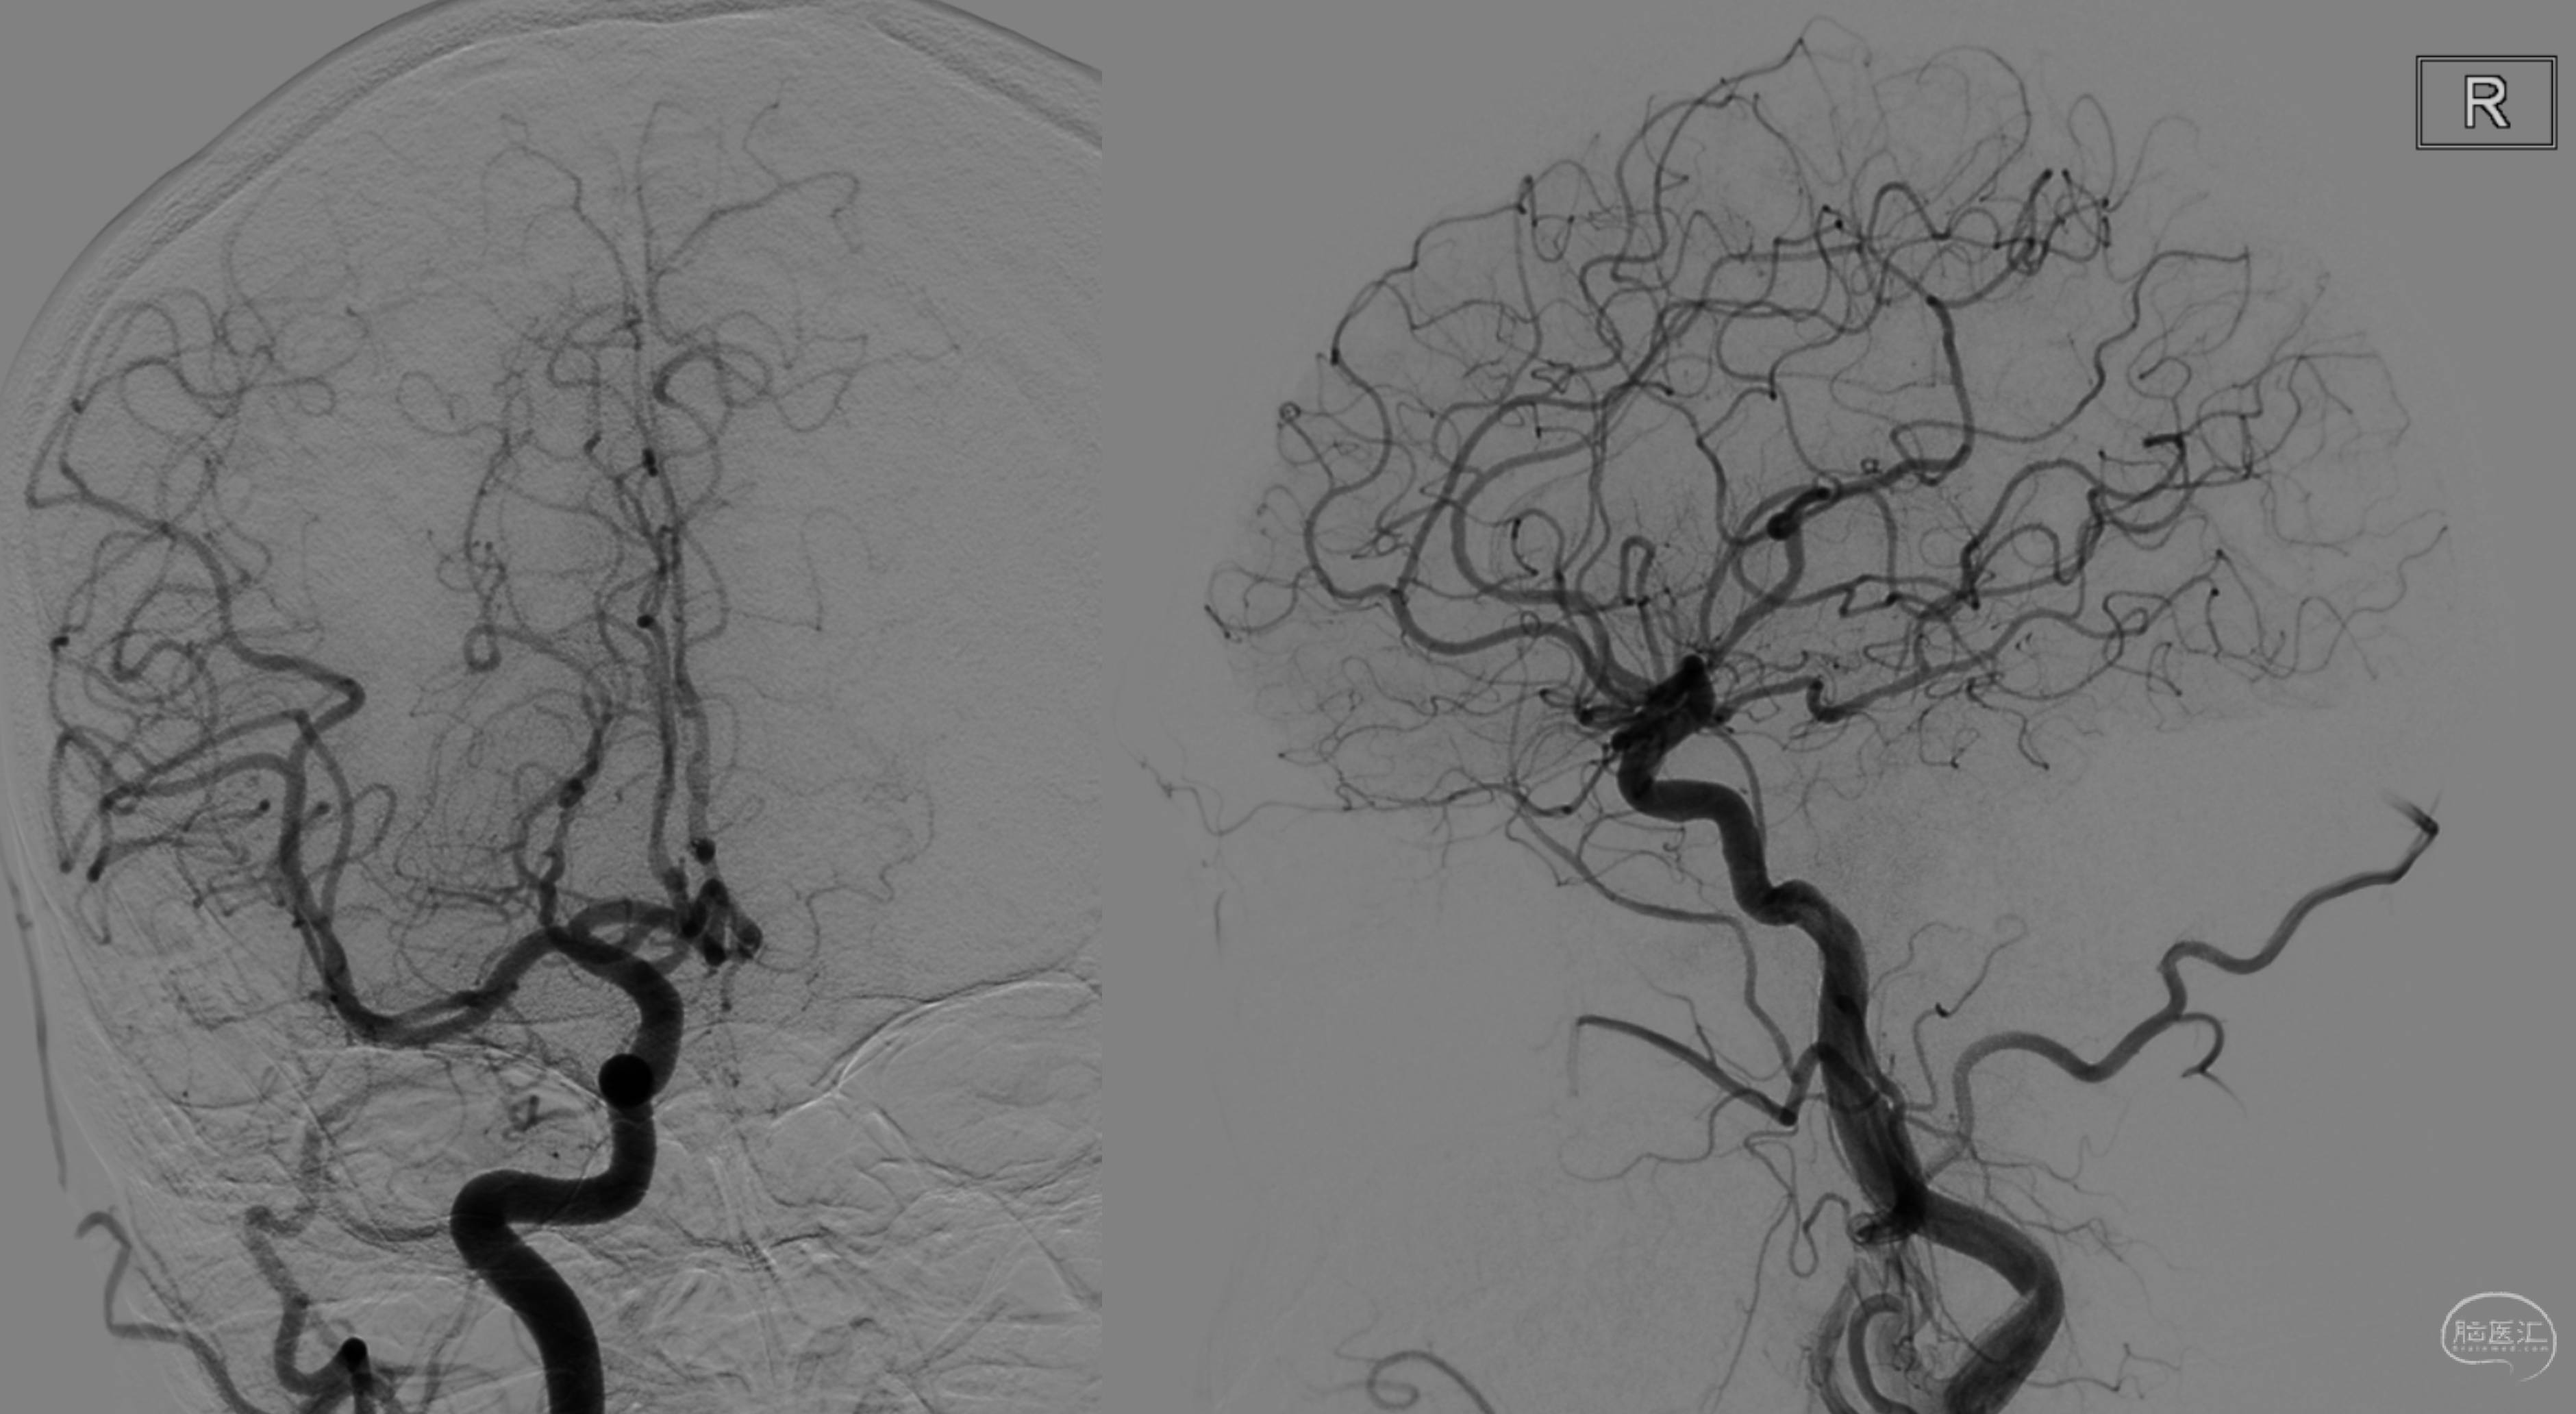

MRA提示左侧椎动脉闭塞,右侧发育不良,颅内段重度狭窄。

DSA造影看到左侧椎动脉V3段通过颈深动脉的肌支吻合代偿供血,但显影一般。

前循环造影提示以后交通开放,向后循环代偿。

右侧ICA主要代偿右侧大脑后动脉。

右侧椎动脉非优势,颅内段发育不良。